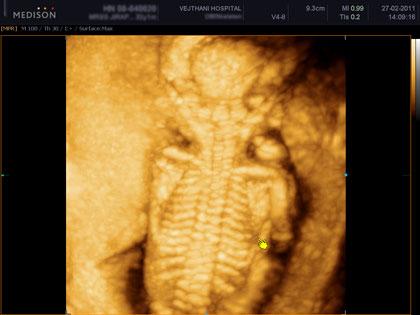

อัลตราซาวด์ 4 มิติ คือการอัลตราซาวด์ 4 มิติ ส่วนใหญ่ก็จะใช้ดูโครงสร้างของเด็ก ดูความผิดปกติ รวมทั้งสามารถดูสีหน้าท่าทางของทารก ซึ่งเป็นอาการตามธรรมชาติของทารก นอกจากนี้ก็ยังสามารถดูโรคที่เป็นความพิการทางโครงสร้าง เช่น ปากแหว่งเพดานโหว่ หัวใจพิการอย่างรุนแรง กะโหลกศีรษะ เป็นต้น ไม่ว่าจะเป็นอวัยวะภายนอกหรือภายใน ก็สามารถดูได้ทั่วทั้งร่างกายของทารก รวมไปถึงการตรวจวัดขนาดของทารก ทั้งนี้จะเป็นประโยชน์อย่างมากกรณีที่พบว่าทารกมีความผิดปกติ แพทย์สามารถวางแผนการรักษาหลังคลอดได้ล่วงหน้า ว่าจะรักษาอย่างไรต่อไป ซึ่งจะทำให้ทารกได้รบการรักษาในทันที

คลิปภาพทารกจากอัลตราซาวด์ 4 มิติ